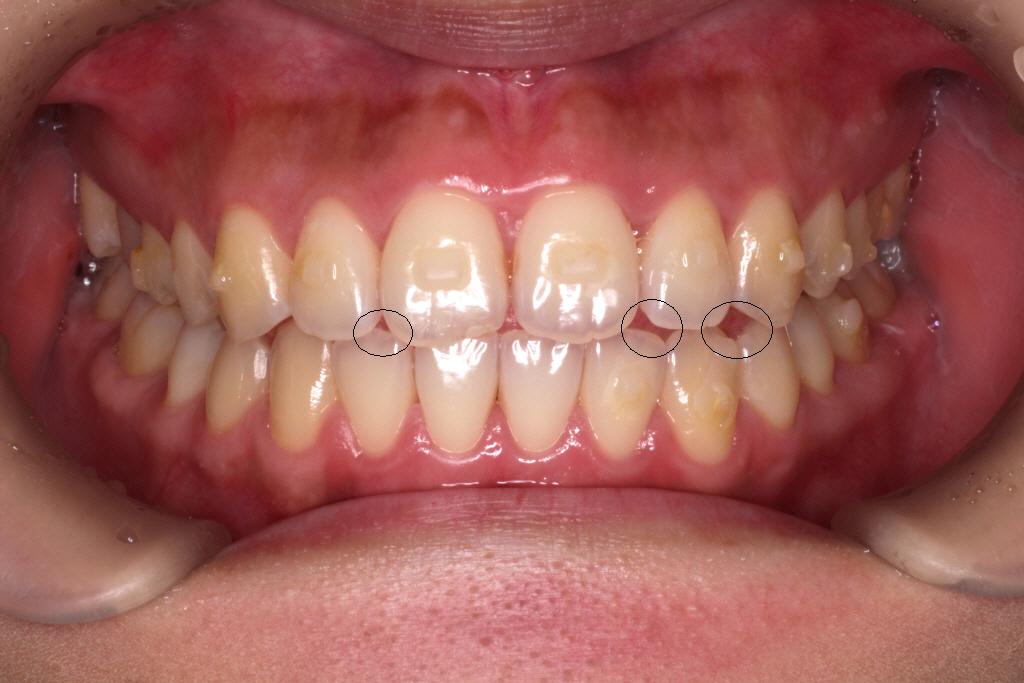

2回目のインビザラインのクリーンチェックです。最後のアライナーの12番です。

上のクリーンチェックでは前歯に隙間は空かない予定でしたが、

私は、舌癖(舌を前に出してしまう)があることがわかりました。

舌を前に出してしまうと、前歯を押してしまうためインビザラインで動かしていくときに妨げになってしまいます。

・長期間にわたって重なっていた歯は、歯間接触下部の歯肉組織が失われている場合があり、歯列矯正を行うことで、「ブラックトライアングル」が発生する可能性があります。